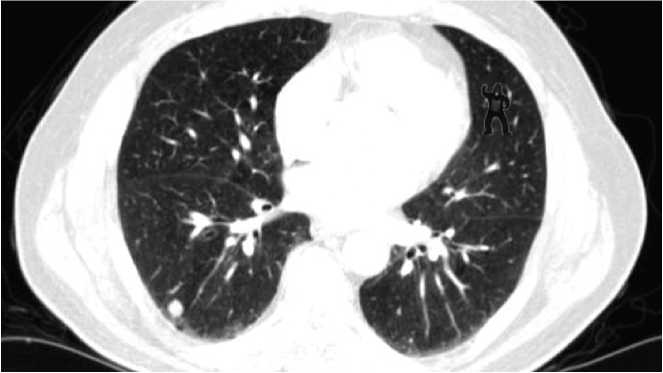

Слепота невнимания — это не просто следствие первого наблюдения незнакомой сцены (например, баскетбольного матча с участием гориллы). Дефект восприятия также распространяется на людей, которые проводили бесчисленные часы, наблюдая одну и ту же сцену снова и снова. Например, было проведено исследование с участием радиологов, которые анализируют компьютерную томографию при диагностике рака легких[132]. Радиологам показали пять снимков компьютерной томографии с опухолевыми узлами и попросили описать их. Небольшое изображение гориллы было помещено в верхний правый квадрант пятого снимка (рис. 6.4). После того как радиологи закончили писать заключение по пятому снимку, им задали три вопроса:

Рис. 6.4. Слепота невнимания в действии

Из 24 участвовавших в исследовании радиологов только 4 (17 %) заметили гориллу. Исследователи отслеживали движения глаз рентгенологов, поэтому они могли опровергнуть предположение о том, что изображение гориллы просто не попало в поле зрения участников — рентгенологи его видели. Но, несмотря на визуально ощущаемые данные, большинство участников не воспринимали гориллу; они искали паттерны, указывающие на рак, и любые другие детали того, что было прямо перед ними, отсеивались где-то на пути между глазами и их сознанием.